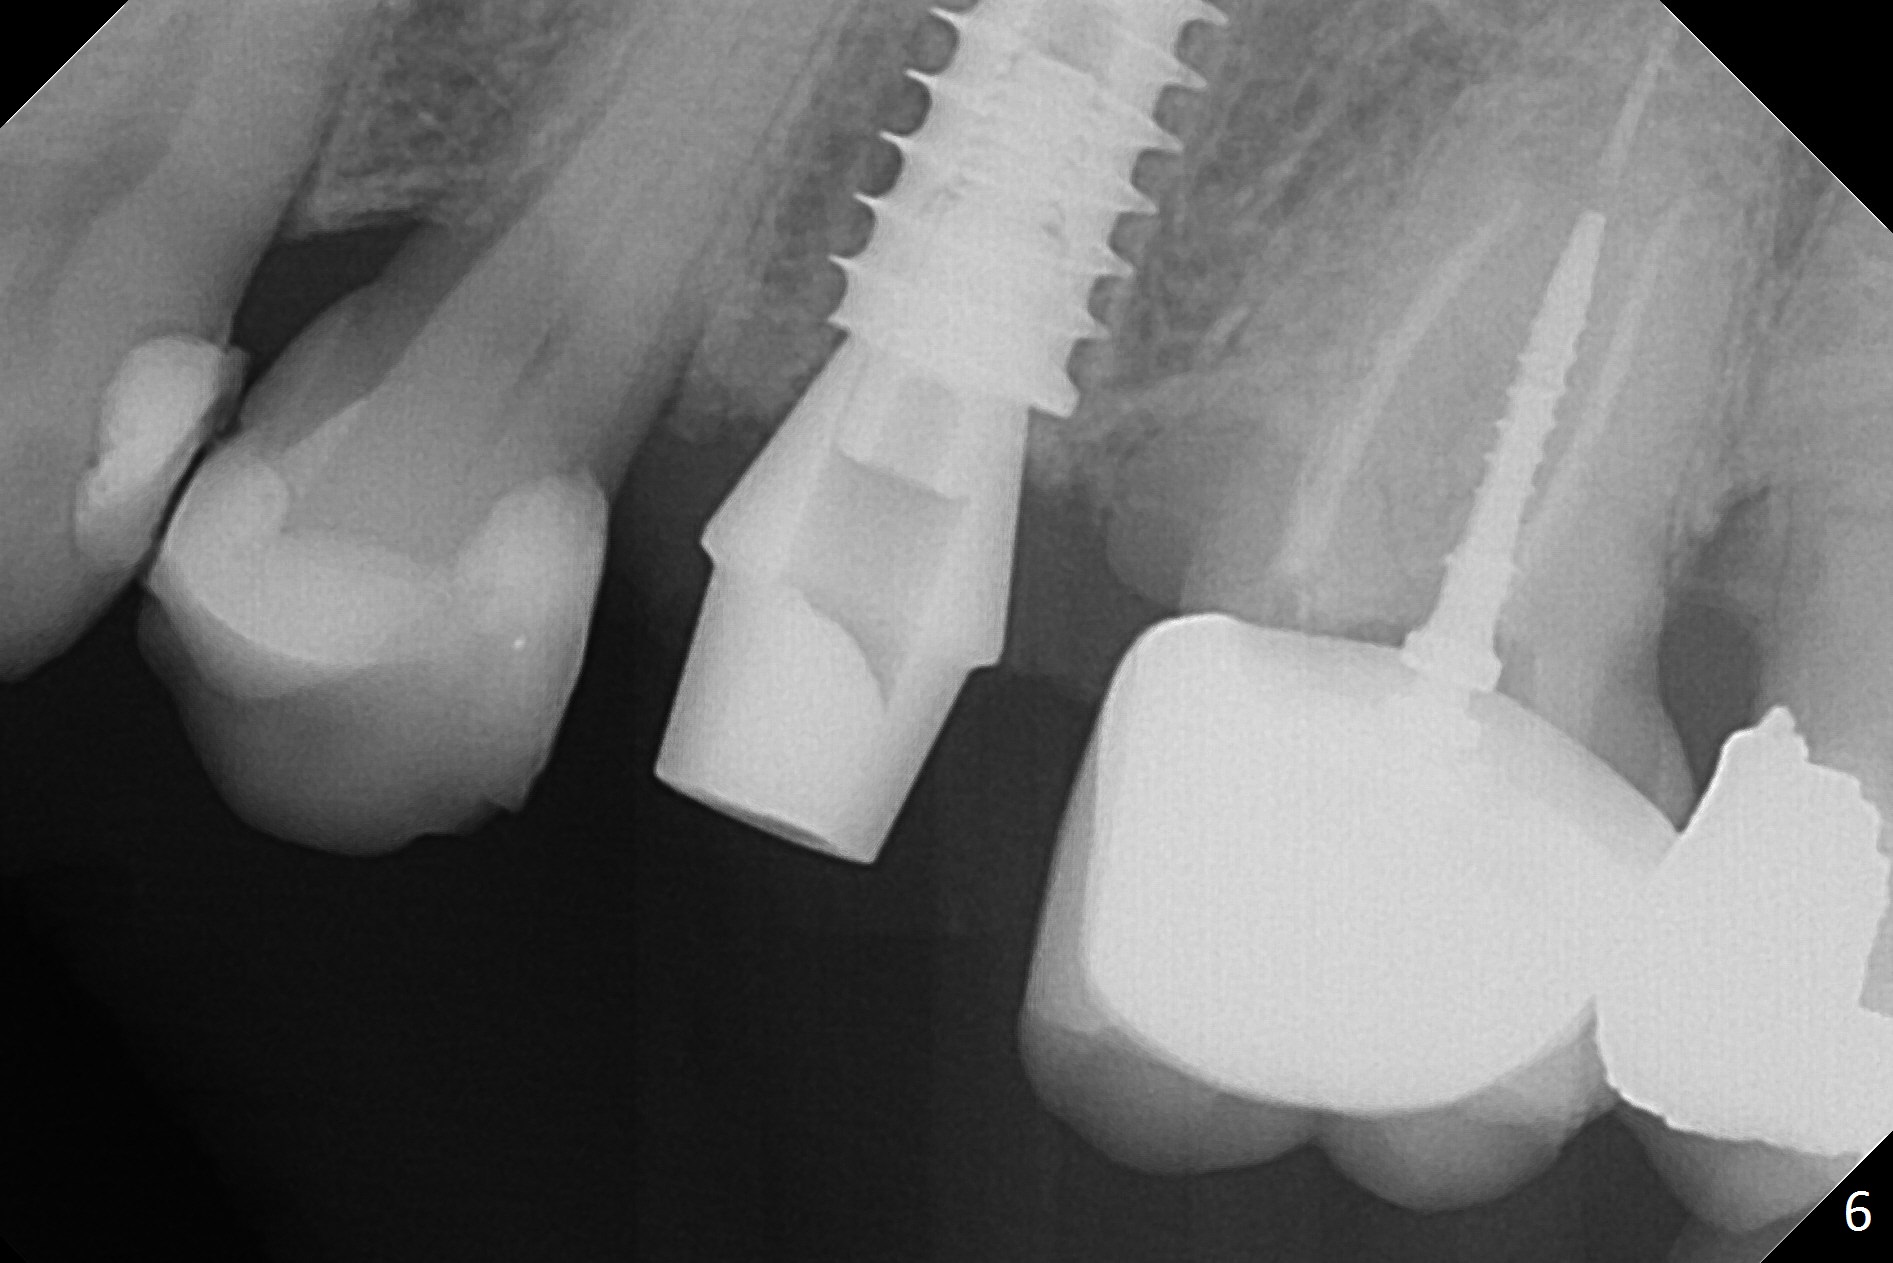

Since the apical native bone is limited at #13 after extraction, no PA is taken until a 4x11 mm dummy implant is placed after 1.6 mm and 3.3 mm drills for 13 mm (Fig.1). After using Lindamann bur to move the osteotomy distal and reusing 3.3 mm drill, the trajectory of a 4.5x11 mm IBS dummy implant improves (Fig.2,3 with low stability). When the implant is removed, the buccal portion of the socket is found to be perforated (Fig.4 P). Although the reason for the perforation is unknown, it is repaired by insertion of a piece of PRF plug, followed by allograft. #1 and 2 in Fig.4 represent the 1st and 2nd osteotomies, as shown in Fig.1 and 2, respectively. The trajectory of the final 5x13 mm implant is acceptable (Fig.5-7, different angulations), so is insertion torque (45 Ncm). After placing a 5.5x4(4) mm abutment, an immediate provisional is fabricated (Fig.8 P) with occlusal clearance (*). The interdental papillae remain in place 12 days postop (Fig.9 *). There is no sign of postop sinus infection. The provisional is loose 18 days postop; the abutment is changed to 5x4(3) mm (Fig.10). It is difficult to catch the mesial margin of the abutment for impression 4 months postop, due to poor oral hygiene and the short cuff (3 mm, Fig.11). The appointment for impression is rescheduled with emphasis on oral hygiene and no wearing the provisional for a few days prior to next appointment. Bone has grown into the space between the 1st and 2nd threads 5 months post cementation (Fig.12) and the bone is normal, solid and dense 2 years 11 months post cementation (Fig.13 >). There is mesial open margin of the tooth #14 (Fig.13,14 *).